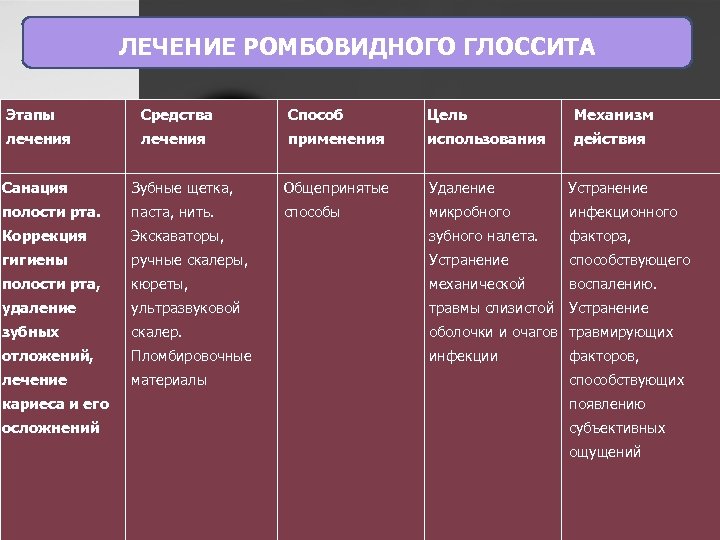

ЛЕЧЕНИЕ РОМБОВИДНОГО ГЛОССИТА Этапы Средства Способ Цель Механизм лечения применения использования действия Санация Зубные щетка, Общепринятые Удаление Устранение полости рта. паста, нить. способы микробного инфекционного Коррекция Экскаваторы, зубного налета. фактора, гигиены ручные скалеры, Устранение способствующего полости рта, кюреты, механической воспалению. удаление ультразвуковой травмы слизистой Устранение зубных скалер. оболочки и очагов травмирующих отложений, Пломбировочные инфекции лечение материалы факторов, способствующих кариеса и его появлению осложнений субъективных ощущений